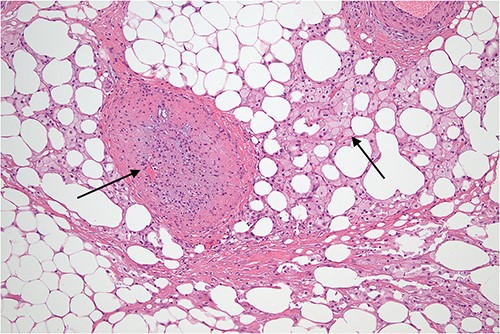

Higher power view demonstrating the thickened fibrous septum with vascular congestion involving small blood vessels.

Slightly off-center nodule representing an obstructed medium sized blood vessel with fibrous occlusion of the lumen. There were several small vessels showing similar features in the biopsy indicating a chronic, possibly recurrent process. The necrosis demonstrated in the adjacent fatty tissue is not typical of mycobacterial infection and is what might follow ischemia, possibly related to omental volvulus or herniation and is indicative of a chronic process.